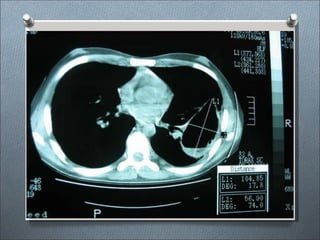

ASPERGILLOSIS PULMONAR INVASIVA

• Enfermedad fulminante con fiebre alta,

consolidación pulmonar y diseminación

hematógena.

• Manifestaciones no comunes incluyen:

endocarditis, sinusitis, endoftalmitis,

osteomielitis, esofagitis, ulceras necrotizantes

de piel, meningitis y abscesos cerebrales.